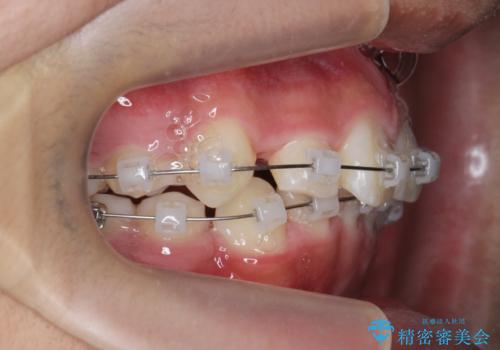

- 前歯のがたつきが原因で歯ブラシしづらい、見た目を改善したい!と矯正治療を希望され来院されました。

スペースの不足が見られるため、小臼歯の4本抜歯を行いマルチブラケットを用いた矯正治療を計画します。

噛み締めが強く、治療に時間がかかりましたが矯正治療の仕上がりに満足いただくことができました。